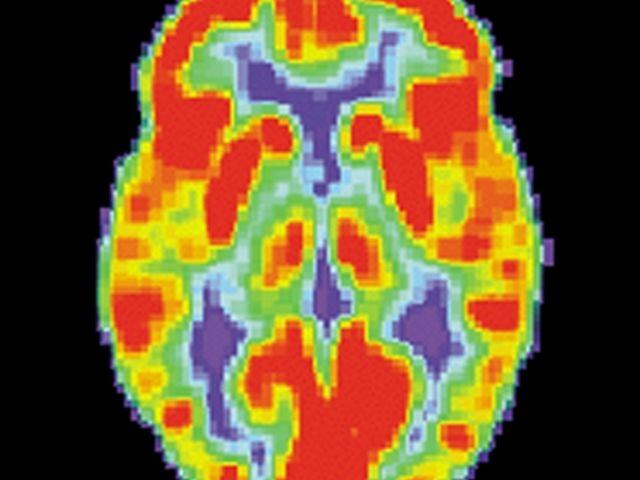

Para ello, la investigación ha tomado en cuenta a más de 2.000 adolescentes, quienes han sido reclutados a partir de los 14 años y se les ha dado seguimiento durante cinco años. Durante este tiempo se les han hecho resonancias magnéticas y otros análisis que revelan imágenes del cerebro.

¿Qué determinaron investigadores? Según el estudio, los científicos notaron cambios en el volumen de dos zonas específicas del cerebro: el putamen y el núcleo caudado. Ambas estructuras forman el llamado cuerpo estriado.

Dentro de sus funciones, el cuerpo estríado se encarga de regular la memoria operativa, la focalización de la atención, la regulación de las conductas y la selección de acciones en torno a la recompensa esperada por una acción.

Las anomalías en esta parte del cerebro están relacionadas con condiciones como la depresión, la ansiedad, el trastorno bipolar, el trastorno obsesivo-compulsivo y las adicciones.